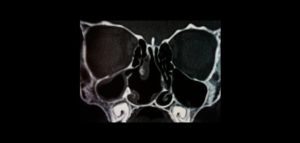

La evaluación mediante imágenes de las variantes anatómicas de los senos paranasales es importante en la evaluación de los factores que predisponen a los cambios

La tomografía de haz cónico (tomografía volumétrica) es una técnica de imagen relativamente común ampliamente utilizado en la región maxilofacial. Además de las anomalías dentales,